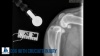

In this image, you'll see that there is a lot of inflammation. That's the white stuff here in the joint. The bones of the knee aren't very smooth. You can see further down there's nice smooth bone. Up at the top here, it's more stippled and reactive, and that indicates that there's been some form of arthritis. So this picture is a great picture of a dog with a cruciate injury. You can also see how the femur up here is sitting much further back on the tibia. It should be sitting further forward.

In comparison to a normal knee, you can see that there isn't all of this inflammation. The bones are a lot smoother, and the femur is sitting a little bit further forward. There are a lot of different treatment options for the repair of this injury. The most common is a surgical repair called a tibial plateau leveling osteotomy (TPLO), a super fancy name for a procedure that gets rid of the need to have a ligament.

We can't repair the ligament. Unfortunately, there's no way to suture it back together or anything like that. So we have to be able to stabilize the knee so that it's not shifting like that when the dog is moving. The way we do that is we make a cut, a curved cut into this lower bone, and then what we'll do is actually shift the bone so that the femur sits further forward on this tibia, and then we hold it in place with a metal bone plate. By doing that, you'll see that I can't get the knee to shift forward anymore, so it'll stabilize the joint for the dog when he's moving. After surgery, you will see how the knee looks with the new placement. You can see the bone plate that we talked about and the cut that we had to make. Then you'll also see how the femur is now sitting further forward on the bone like it should. This is how the knee is stabilized after surgery.